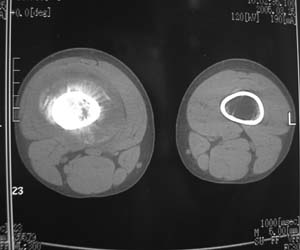

股骨下段针状瘤骨垂直于骨皮质向外生长.并见软组织密度肿块影.骨髓腔密度增高.考虑股骨下段成骨肉瘤.胸膜及左肺转移瘤.

支持---股骨下段针状瘤骨垂直于骨皮质向外生长.并见软组织密度肿块影.骨髓腔密度增高.考虑股骨下段成骨肉瘤.胸膜及左肺转移瘤.

支持:股骨下段针状瘤骨垂直于骨皮质向外生长.并见软组织密度肿块影.骨髓腔密度增高.考虑股骨下段成骨肉瘤.胸膜及左肺转移瘤.